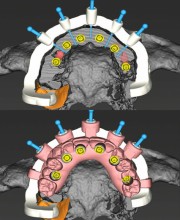

- استفاده از اسکن دیجیتال و تصویربرداری سهبعدی (CBCT) برای تشخیص دقیق وضعیت استخوان و برنامهریزی درمان

- امکان انجام بازسازی استخوان و جراحی ایمپلنت بهصورت همزمان، در صورت فراهم بودن شرایط فک بیمار

- کاهش نیاز به جراحیهای مجدد از طریق طراحی دقیق و اجرای اصولی مراحل درمان